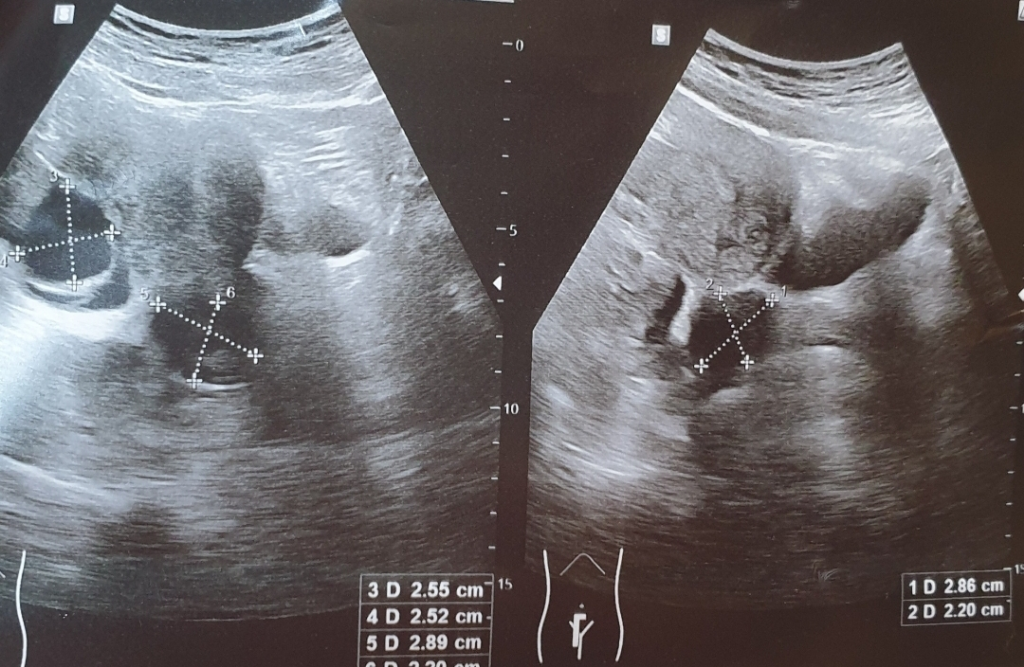

대장이나 s장 에 물혹? 용종? 이 있다면(크기가 3cm정도로 크면? ). 하복부 초암파로 로도 발견이 될수 있나요?

대장에 3cm 암도 보이나요?

용종과 암이 복부초음파상에서 다르게 보이는지. 비슷하거나 같게 보여서 구분을 할수 없는지 궁금합니다

대장쪽에 크기가 3cm 정도 크기의 혹이 있는 것이 하복부 초음파 검사를 통해서 우연히 발견될 수도 있습니다. 그렇지만 초음파 소견을 통해서 정확하게 그냥 양성인 용종인지 암 종양인지 구분이 가능하지는 않습니다. 조직검사를 확인해보아야 합니다.